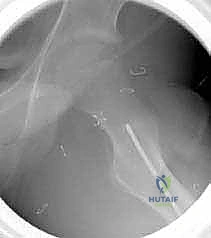

5. التدوير (Derotation)

هنا تكمن مهارة الجراح؛ يتم تدوير الجزء السفلي من عظم الفخذ (الساق بأكملها) إلى الخارج بالدرجة المطلوبة تماماً (عادة بين 20 إلى 30 درجة) لتصحيح الانحراف الأمامي المفرط وإعادة القدم إلى وضعية الاستقامة الطبيعية.